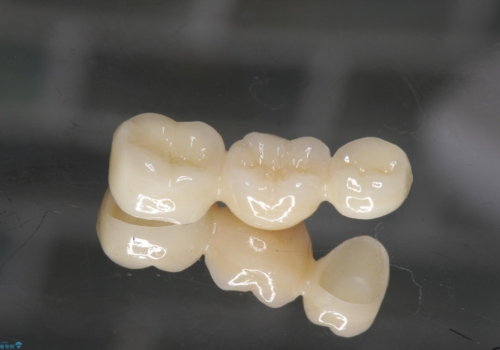

- 36.3万円 (ジルコニアクラウン 10万円×3、仮歯1万円×3)費用は治療当時の料金となります

途中全体矯正をはさみ、根の向きが並行になった状態でブリッジを入れることができました。